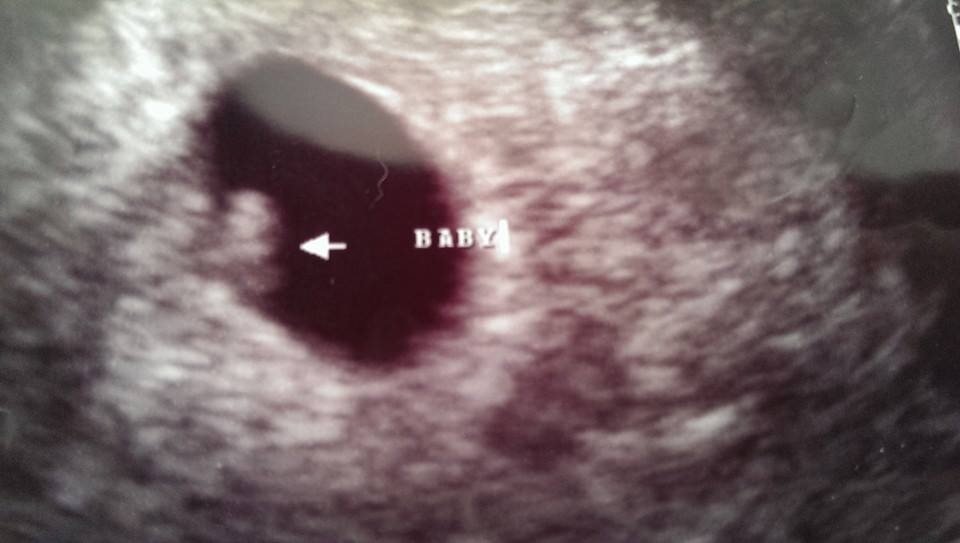

I thought my baby making days were long over. Recently found out that I am pregnant at 44 with number 5. My other children are 16g, 19b, 20b, and 26 b.

Had my first us last Monday to rule out ectopic (had one over 20 years a go) baby is in the right place and we even saw/ heard the heartbeat.

Still super nervous as I realize to higher risk of miscarriage at my age. The shock is gone for the most part and I'm trying to allow myself to get excited. Holding my breath until I hit that 12 week mark.